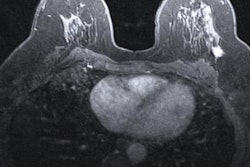

Preoperative MRI is tied to reduced risk of breast cancer recurrence in patients aged 50 years or younger with cancer diagnosis and for hormone receptor-negative cancers, research presented December 1 at the RSNA annual meeting found.

Yoen and colleagues wanted to explore and compare the effect of preoperative MRI on recurrence and survival outcomes in young women with breast cancer diagnoses. They also looked at the interaction between preoperative MRI and breast cancer hormone receptor status.

The researchers reviewed data collected from 2012 to 2015 from 1,778 patients. Out of these, 1,653 patients (93%) had undergone MRI and 125 patients (7%) did not. They matched and balanced patients without preoperative MRI with women who had preoperative MRI.

On a median follow-up of seven years, the researchers reported that the cumulative cancer recurrence rate was 7% (n = 105). Eleven of these cases (9%) came from the non-MRI group while 94 cases (6%) came from the MRI group. The team found a significant association in the matched cohort between MRI and a lower risk of total recurrence; the group of patients who had received preoperative MRI had a hazard ratio (HR) of 0.4 for total recurrence compared with the control group (p = 0.018).

Also, patients who received MRI had a significantly higher recurrence-free survival rate (95.6%) compared with those who didn't get an MRI (89.1%). Yoen said this was mainly due to improved local-regional recurrence rates. However, MRI was not significantly associated with improved overall survival (p = 0.875).

Delving further into the data, the researchers also found a significant association for MRI for decreasing the risk of total recurrence in patients specifically with hormone receptor-negative breast cancer (HR, 0.2; p < 0.01). However, they did not find a significant benefit for patients with hormone receptor-positive cancers (HR, 1.3; p = 0.64).

Yoen said the preoperative breast MRI strategy could be especially helpful for women with hormone receptor-negative cancers as departments try to improve upon breast MRI guidelines.